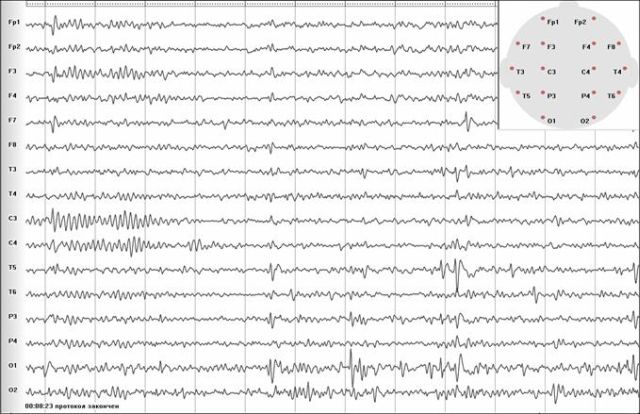

ЭЭГ основана на определении разности электрических потенциалов, генерируемых нейронами, и позволяет регистрировать патологические разряды и волны на коре головного мозга во время приступа и в межприступном периоде. Запись ЭЭГ осуществляется путем наложения электродов над головным мозгом. Наиболее часто пользуются схемой наложения электродов является «10%-20%».

Определение зоны начала приступа (фокальное или генерализованный), его распространение по коре головного мозга, дают возможность докторам выбрать оптимальную тактику лечения. Анализ биоэлектрической активности мозга проводится с использованием специальных монтажей: биполярные и монополярные.

Наиболее типичными патологическими изменениями на ЭЭГ (эпилептиформная активность) выявляемыми у пациентов с эпилепсией являются:

— пики, «спайки» («spike») — эпилептиформный феномен, отличный от основной активности и имеющий пикообразную форму. Период пика составляет от 40 до 80 мсек. «Спайки» могут наблюдаться при различных формах эпилепсии. Одиночные пики встречаются редко, обычно они предшествуют появлению волн. Сами пики отражают процессы возбуждения нейронов, а медленные волны – процессы торможения.

— острые волны («Sharp-waves») – данный феномен также как и «спайки» имеет пикообразную форму, но период его более длительный, составляет 80-200 мсек. Острые волны могут встречаться изолированно (особенной при фокальных формах эпилепсии) или предшествовать медленной волне. Феномен является высоко специфичным в отношении эпилепсии.

— комплексы «спайк-волна» (синоним «пик — медленная волна») – паттерн состоящий из пика и следующей за ним медленной волной. Как правило, данная активность имеет генерализованный характер и является специфичной для идиопатических генерализованных форм эпилепсии. Однако, может встречаться и при фокальной эпилепсии в виде локальных единичных комплексов.

— множественные пики, полипики, «полиспайки» — группа следующих друг за другом 3-х и более пиков частотой от 10 Гц и выше. Генерализованные полипики могут являются специфическим паттерном для миоклонических форм эпилепсии (таких ка юношеская миоклоническая эпилепсия и т.д.).